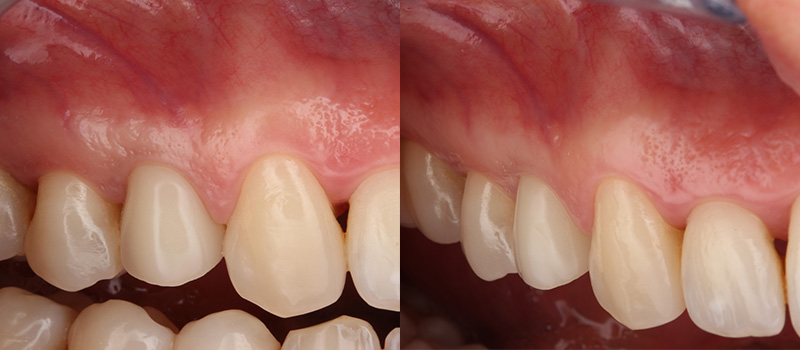

Après 4 mois de cicatrisation, la couronne d’usage transvissée avec une armature zircone peut alors être réalisée.

Fig. 06 : situation clinique à 4 mois de cicatrisation vue vestibulaire et vue latérale.